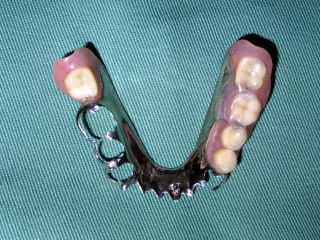

<金属のプレートの入れ歯を使えば

歯周病で弱った歯を護れます> |

取り外し式の入れ歯は手入れが面倒で歯に悪いものと思っていませんか?

金具と一体型の薄い金属の板でできたメタルプレート義歯は、装着時の違和感が少なく、歯周病でぐらぐらになった弱った歯を固定して護る効果があります。

コルセットのような装具ですので、ご興味のある方は一度ご相談ください。 |

| メタルプレート義歯の写真 |